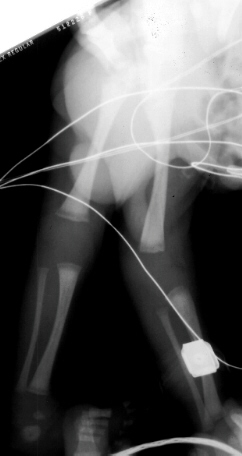

This 29 week gestation male was born by vaginal delivery. These x-rays were made after it was noted that that the knees appeared to be hyper-extended. The right knee had -30 degrees extension to 20 degrees of flexion. The left knee had -20 degrees extension to 20 degrees of flexion. Ortolani exam revealed a positive sign in the left hip and a negative sign in the right. Knee splints were applied. In two weeks the knees were able to flex to 75 degrees bilaterally.